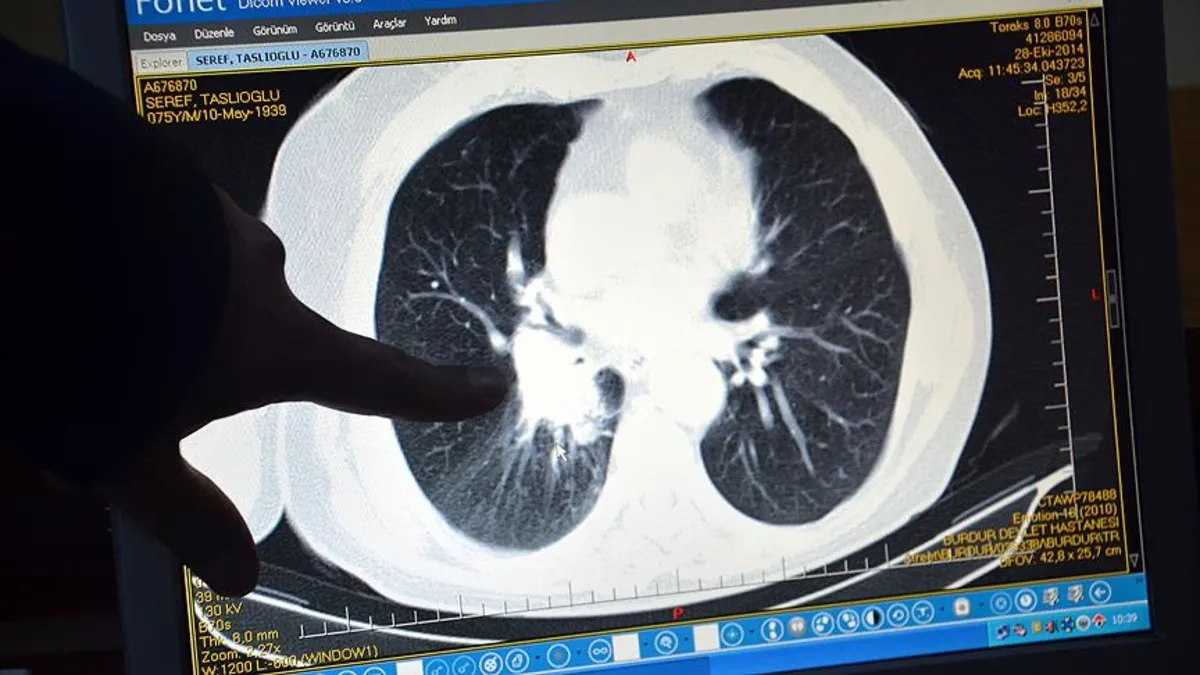

Akciğer kanseri, tüm kanser türleri arasında en yüksek ölüme yol açan hastalık olarak dikkat çekiyor. Göğüs Cerrahisi Uzmanı Opr. Dr. Volkan Yılmaz, akciğer kanseri hakkında bilgilendirmelerde bulundu.

Akciğer kanserine yakalanan hastaların çoğunun tanı anında semptomatik olduğunu belirten Opr. Dr. Yılmaz, "Sıklıkla öksürük, nefes darlığı, hemoptizi (kanlı balgam) ve göğüs ağrısı gibi spesifik belirtilerle başvuran hastalarda; halsizlik, kilo kaybı ve ateş gibi non-spesifik şikayetler de görülebilmektedir. Uzmanlar, akciğer kanserinin erken teşhis edilmesinin tedavi başarısını önemli ölçüde artırdığını vurguluyor. Son yıllarda tanı ve tedavi tekniklerinde yaşanan gelişmeler, minimal invaziv yöntemler ve hedefe yönelik tedaviler, bu kanser türüyle mücadelede önemli bir fark oluşturmaktadır" dedi.